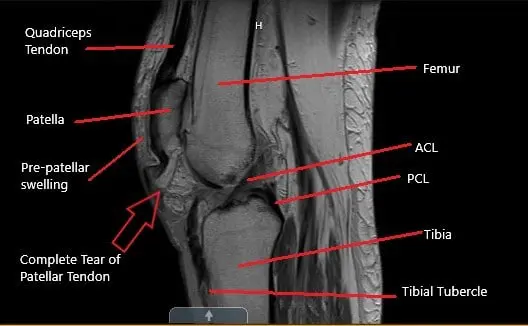

MRI of the knee in the sagittal section showing a complete tear of the patellar tendon

MRI of the left knee suggested a full-thickness midsubstance tear of the patellar tendon with approximately 1.7 cm fluid gap and associated patella Alta. There was diffuse infiltration/edema within the infrapatellar and prepatellar fat. The patient is a retired banker and had an active lifestyle before the injury.